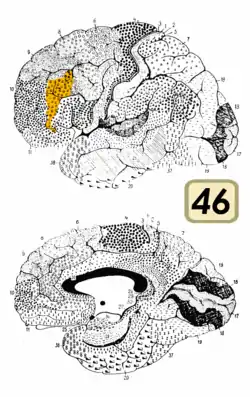

Brodmann area 46, or BA46, is part of the frontal cortex in the human brain. It is between BA10 and BA45.

BA46 is known as middle frontal area 46. In the human brain it occupies approximately the middle third of the middle frontal gyrus and the most rostral portion of the inferior frontal gyrus. Brodmann area 46 roughly corresponds with the dorsolateral prefrontal cortex (DLPFC), although the borders of area 46 are based on cytoarchitecture rather than function. The DLPFC also encompasses part of granular frontal area 9, directly adjacent on the dorsal surface of the cortex.

Cytoarchitecturally, BA46 is bounded dorsally by the granular frontal area 9, rostroventrally by the frontopolar area 10 and caudally by the triangular area 45 (Brodmann-1909). There is some discrepancy between the extent of BA8 (Brodmann-1905) and the same area as described by Walker (1940).[1]

Frontal view.